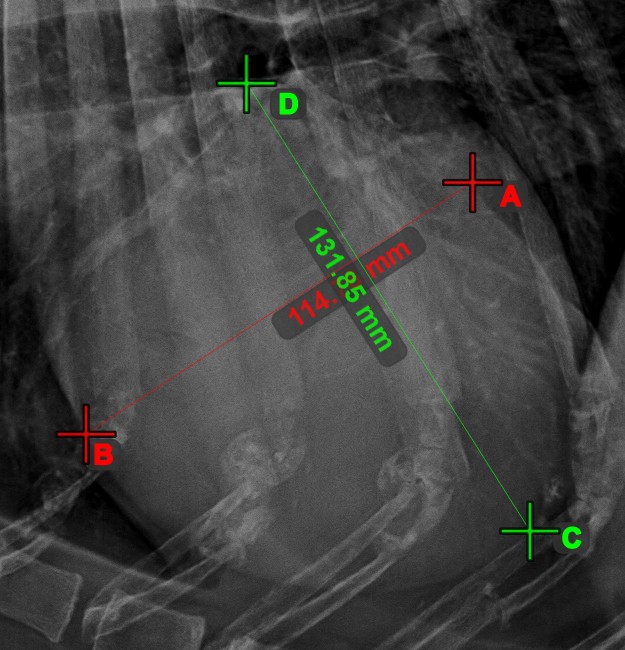

Mittlerer Punkt der Linie¶

Bestimmen und markieren Sie den Mittelpunkt einer neuen oder vorhandenen Linienmessung in der Szene mit dem Werkzeug Mittlerer Punkt der Linie

.

Wählen Sie das Werkzeug aus der linken Symbolleiste aus und weisen Sie es einer der verfügbaren Maustasten zu. Setzen Sie die Start- und Endpunkte in der Szene, wählen Sie sie aus bereits vorhandenen Punkten im Bild aus oder wählen Sie eine bereits gezeichnete Linie aus der Szene. Der Mittelpunkt der Linie wird automatisch berechnet und in der Szene platziert. Der Mittelpunkt jeder Linie wird stets mit dem Buchstaben C markiert.